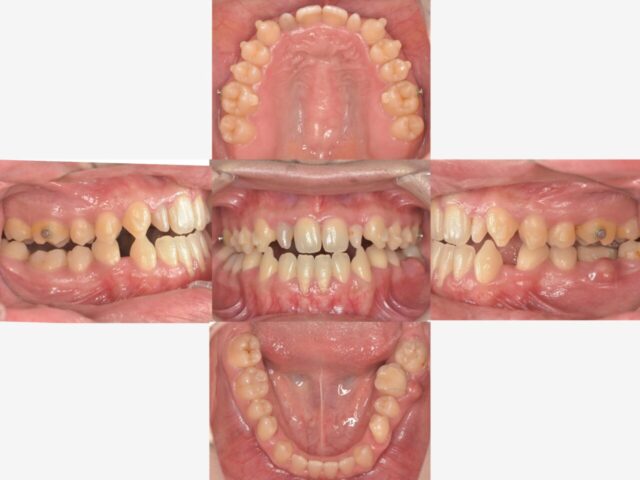

こちらが全体の写真です。

主訴の左下の歯を見てみましょう。

歯茎がパンパンに腫れています。